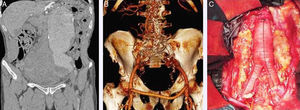

El período de estudio fue de 12 años, desde enero de 2002 a diciembre de 2014. Para la obtención de datos se revisaron las historias clínicas. Se estudiaron 82 casos en total, divididos en dos cohortes, una para los AAAr intervenidos mediante EVAR y otra para los intervenidos mediante cirugía abierta. El tipo de intervención se decide en función de las características del paciente, la anatomía del aneurisma y las preferencias del cirujano correspondiente (fig. 1).

A) Imagen angio-TC que muestra aneurisma de aorta abdominal infrarrenal roto asociado a aneurisma iliaco izquierdo. B) Imagen angio-TC que muestra la correcta colocación de un EVAR aortomonoiliaco asociado a baipás femorofemoral. C) Cirugía abierta con realización de resección aneurismática más injerto aortobiiliaco.